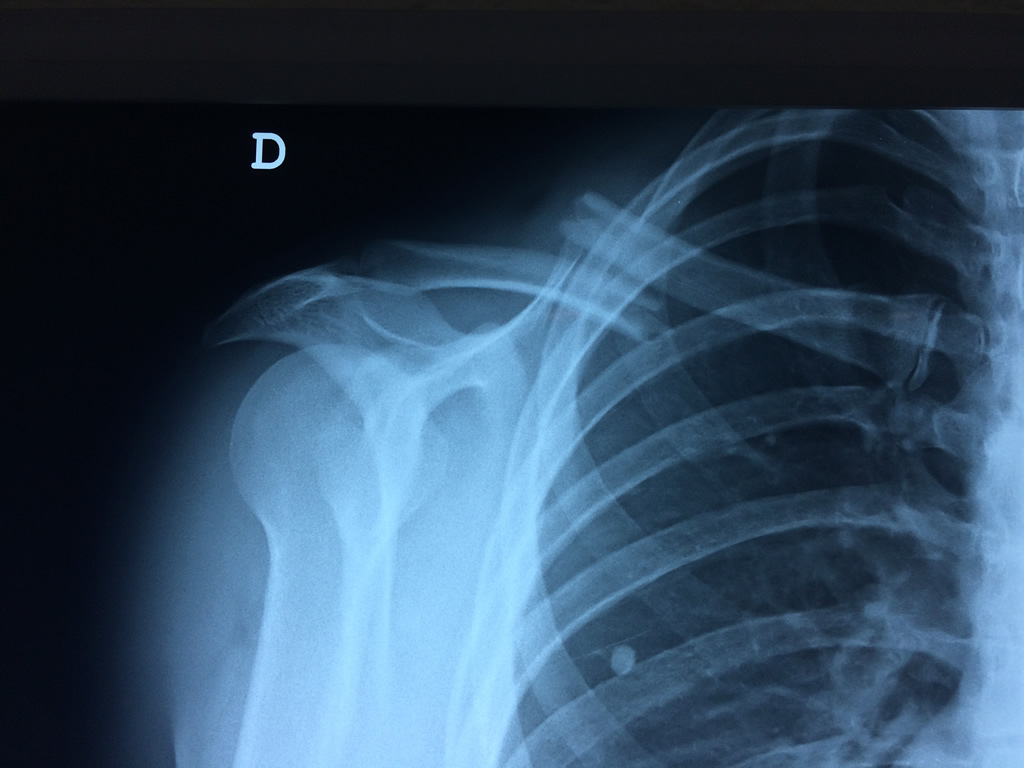

Cirugias en El Salvador - Clavícula

La clavícula es un hueso largo, con forma de "S" itálica, situado en la parte anterosuperior del tórax. Junto con la escápula forman la cintura escapular. Se puede palpar por toda su longitud y se extiende del esternón al acromion de la escápula, siguiendo una dirección oblicua lateral y posterior.